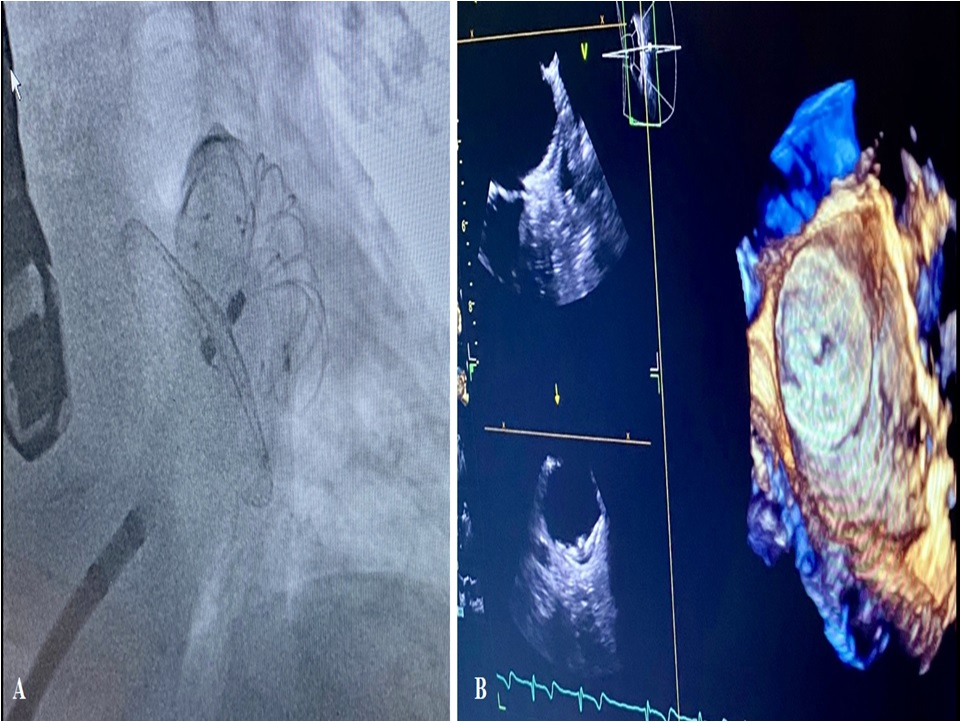

This procedure can be performed successful concomitant procedure as TT epicardial left ventricular lead implantation for cardiac pacemaker/implantable automatic defibrillator cardiac resynchronization device also [69] (Fig. 4).

Fig. 4.A case of TT concomitant LAA exclusion closure and left ventricular epicardial lead implantation. (A,B) Describes TEE monitoring before and after TT LAA exclusion with AtriClip device. (C) Describes antero-posterior chest x-ray image after LAA exclusion and epicardial LV implantation. (D) Highlights image of LAA exclusion and epicardial left ventricular epicardial lead before left lung was re-expansion.